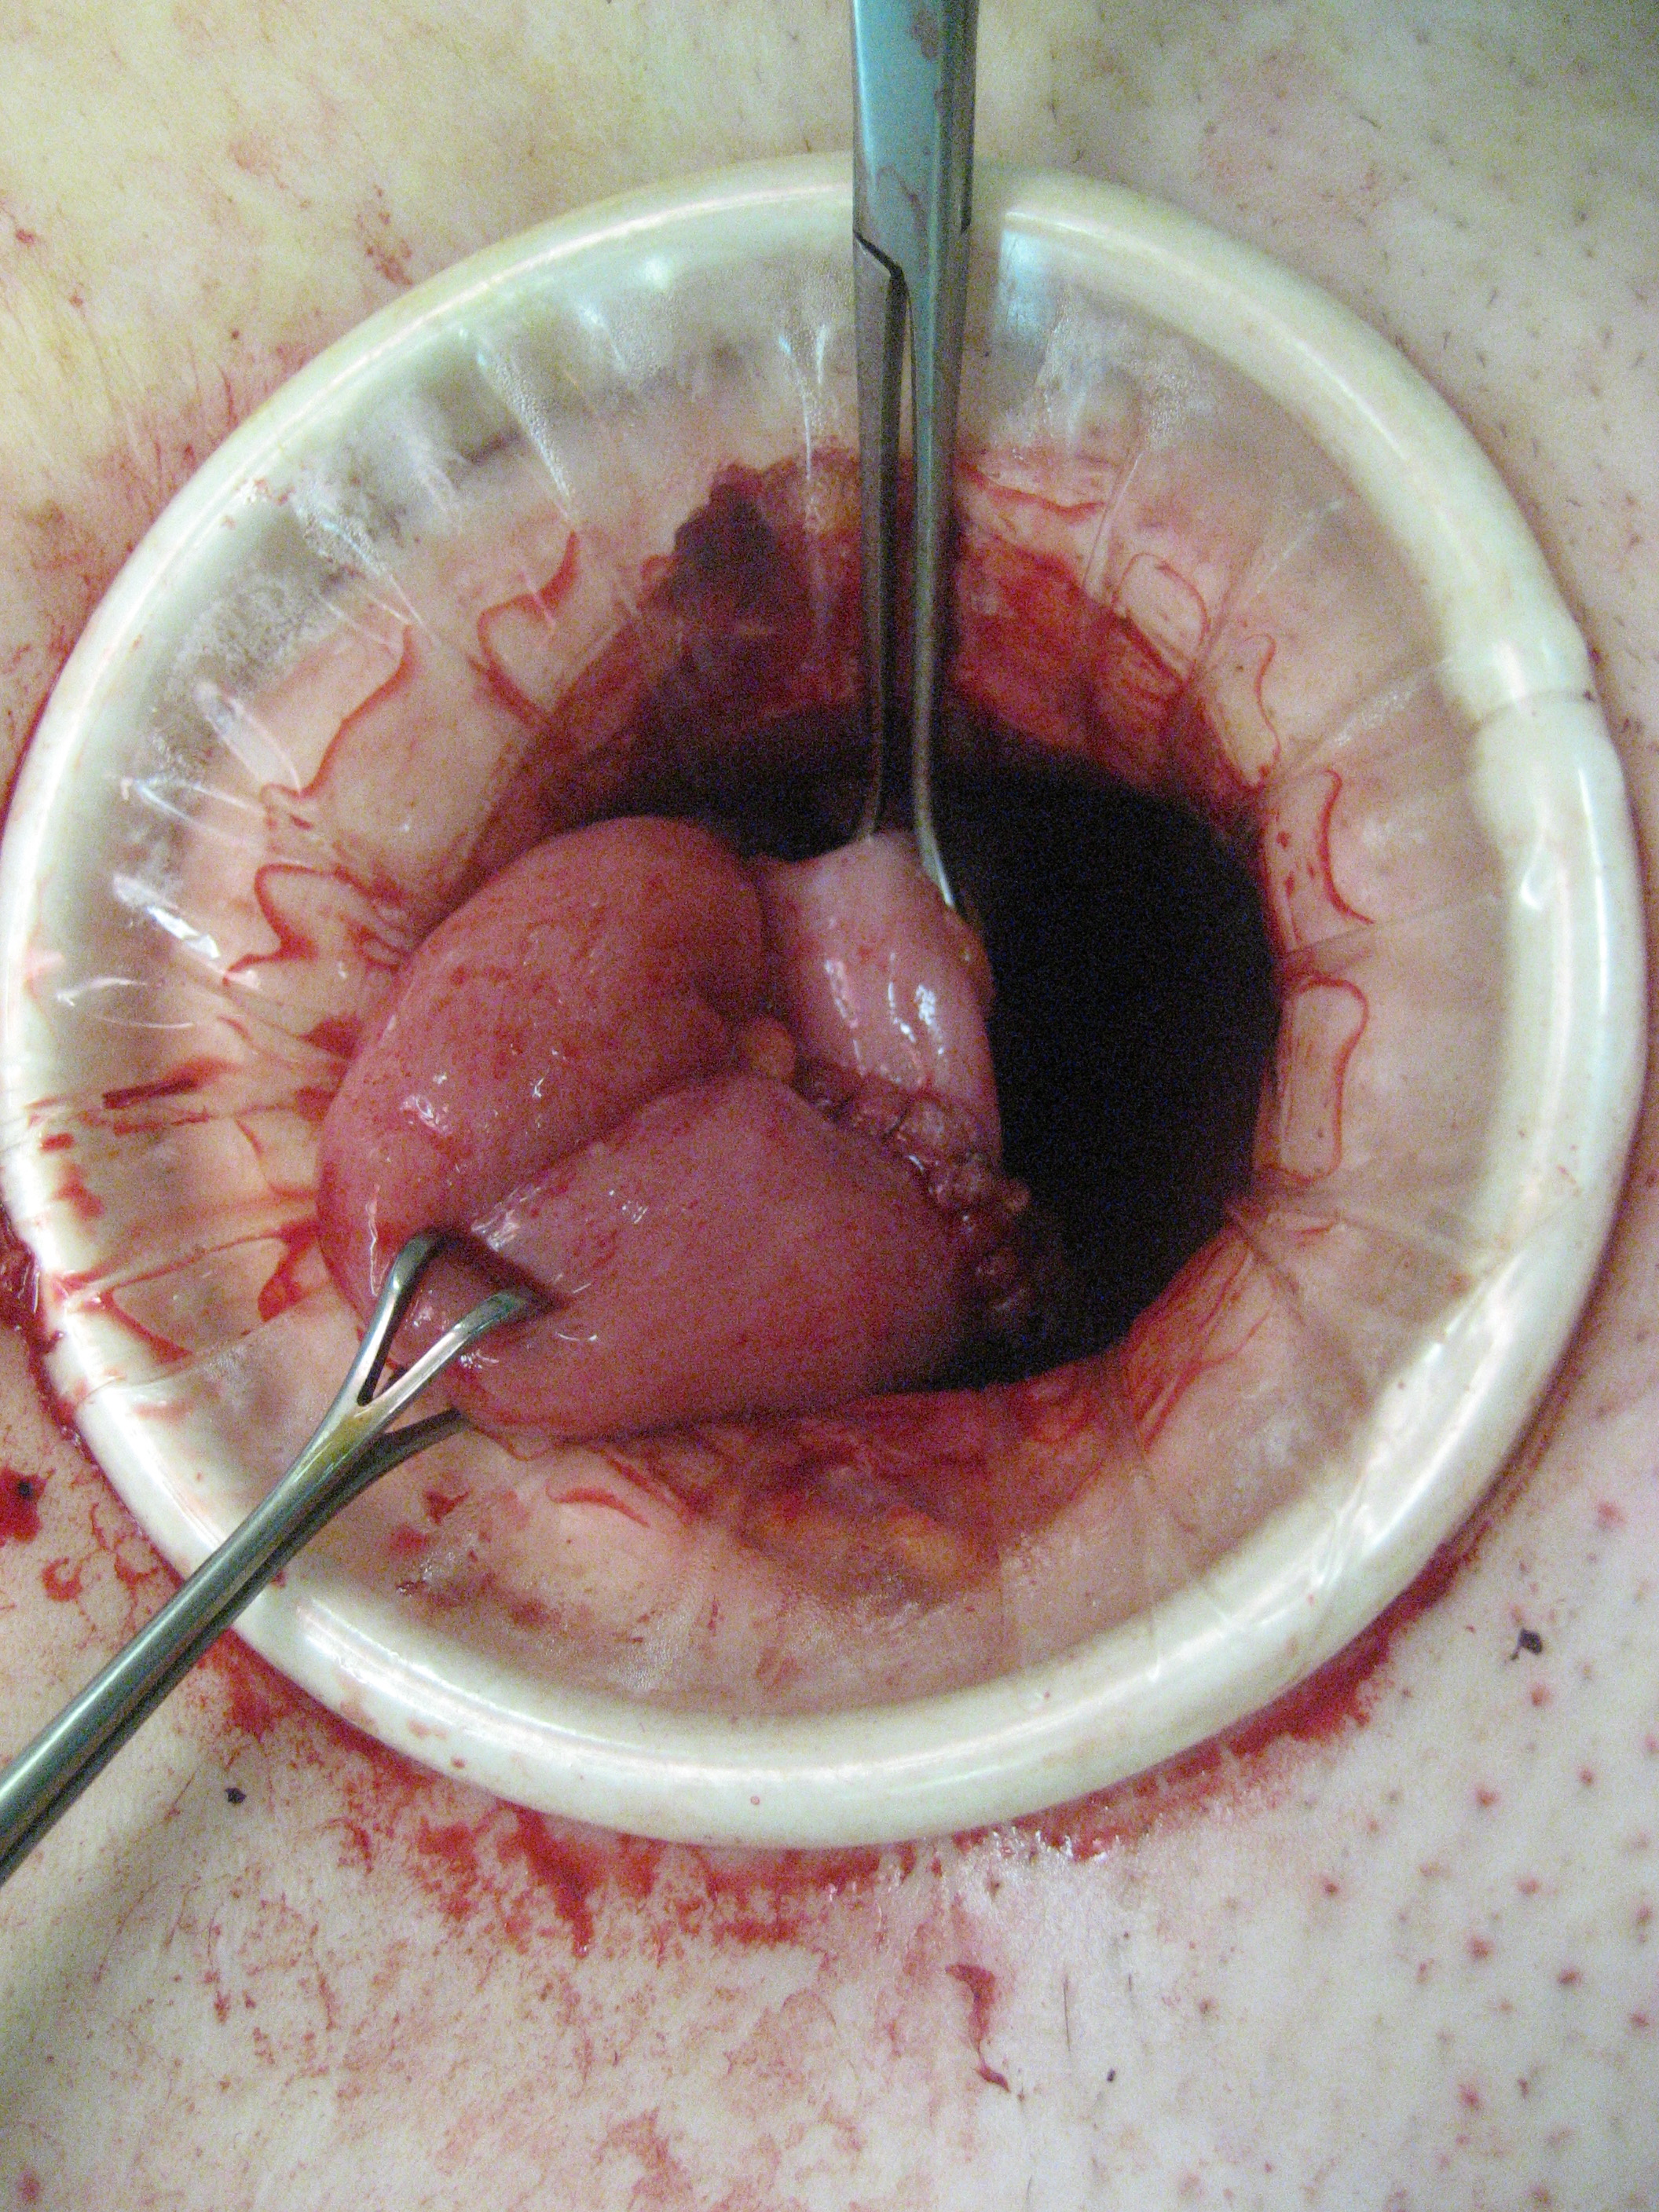

Colorectal cancer affects approximately 1:20 of the population and in South Africa is largely managed by general surgeons. Management of this disease has undergone very significant changes over the last two decades. Until very recently, only two academic general surgery departments included a specialist colorectal unit, and this remains so in the majority of our universities. This has resulted in a generation of surgical graduates who are unfamiliar with, and unskilled in current best management practices for this disease. Rectal cancer is particular challenging and attracts extremely high morbidity and mortality, with poor oncological outcomes. Repeatedly, outcome has been shown to be worse in the hands of generalists, rather than specialist colorectal surgeons, of whom there are very few in the country. This review presents the most important advances of the last 20 years and highlights current controversies and frontiers.